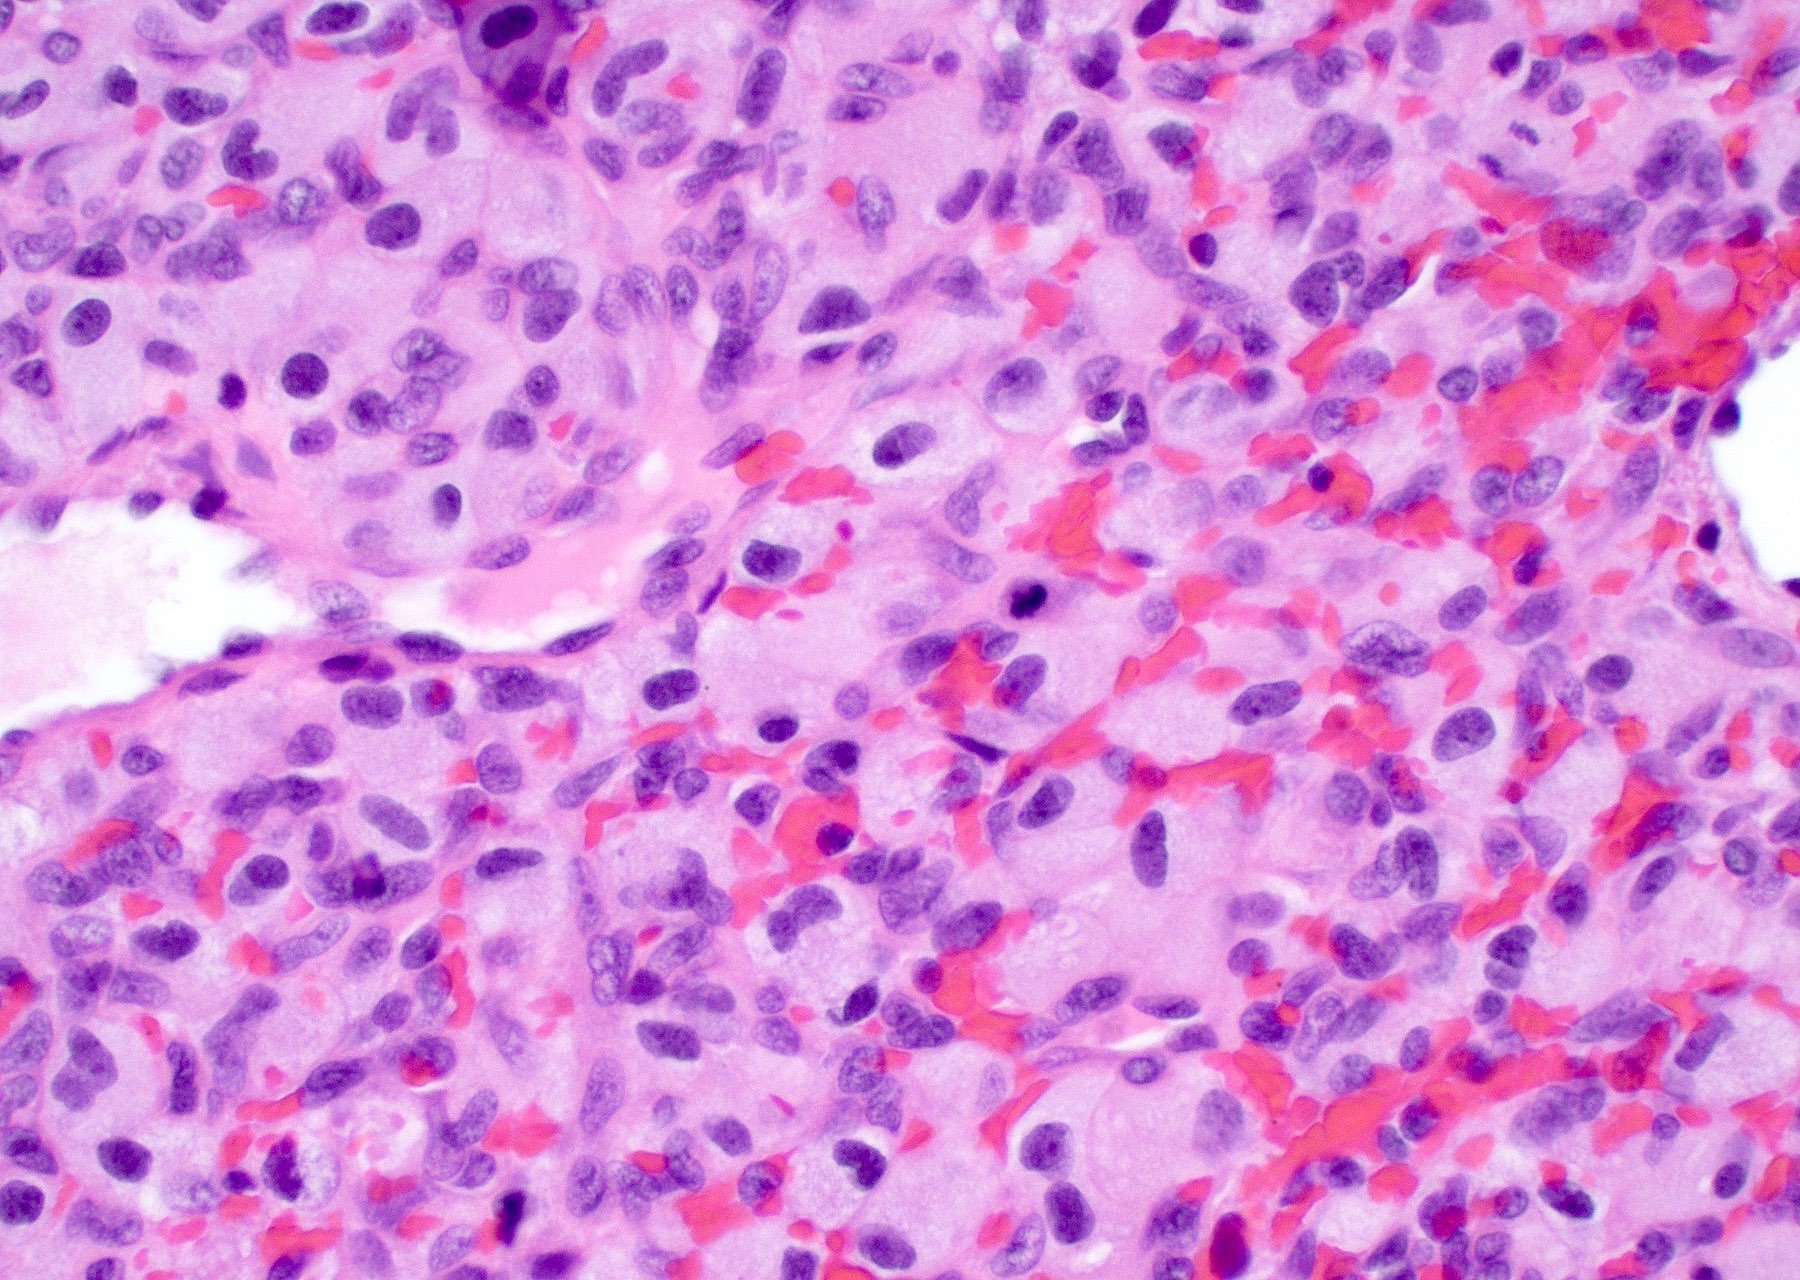

Frozen section description

- Hypercellular infiltrative lesion with variable morphology

- Infiltration often difficult to assess on frozen sections but entrapped neurons may be useful

- Nuclear hyperchromasia and nuclear elongation, possible giant cells

- Mitotic activity

- Necrosis; geographic or pseudopalisading

- Microvascular proliferation

Intraoperative frozen / smear cytology images

Microscopic (histologic) description

- Infiltrating, hypercellular astrocytic neoplasm often with hyperchromatic, elongated nuclei and irregular nuclear membranes

Microscopic (histologic) images

Contributed by Bharat Ramlal, M.D. and Meaghan Morris, M.D., Ph.D.